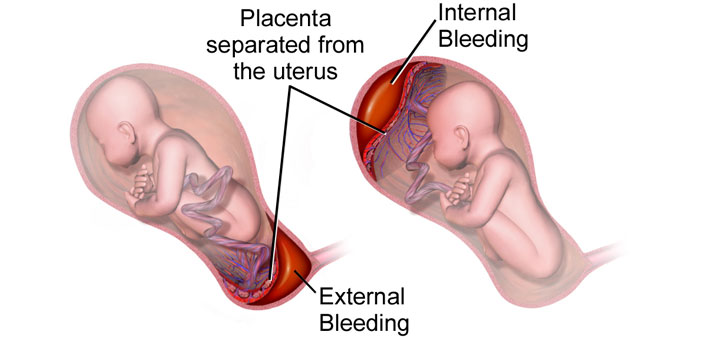

গর্ভাবস্থায় চিন্তিত হবার ৩টি লক্ষণ আপনার জানা আছে কি?

0 SHARES Share Tweet প্রেগন্যান্সি প্রতিটি মহিলার জন্য একটি বিস্ময়কর অভিজ্ঞতা, কিন্তু দুর্ভাগ্যবশত সকল নারী ঐ ম্যাজিকাল...